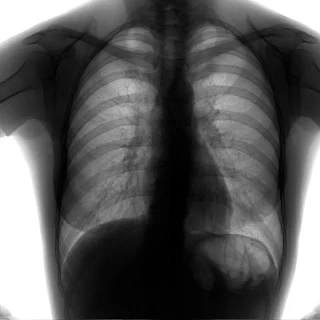

Флюорограма №75

Легені без вогнищево - інфільтративних змін. Корені не змінені. Синуси вільні. Серце норма.